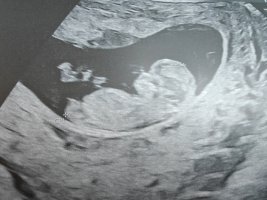

Nub-teorian mukaan sukupuolen voi määrittää jo nt-ultrassa genitaalikyhmyn asennon perusteella. Voit lukea aiheesta lisää täältä.

Kiinnostaako teitä sukupuolen määrittäminen kyseisen teorian avulla? Katsotteko ultrakuvia sillä silmällä?